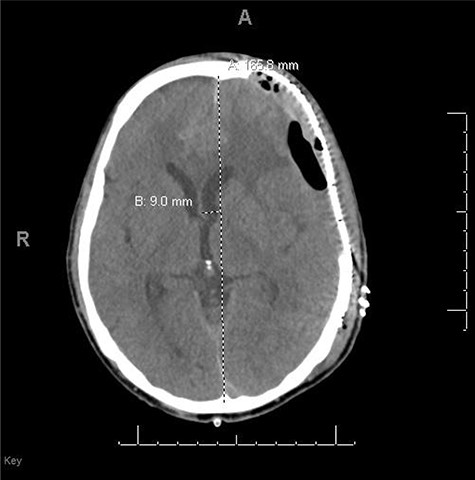

A 59-year-old male was found in the street with a head laceration. He was brought to the trauma bay as a pedestrian struck trauma patient with a prehospital GCS of 3. On arrival, his GCS was 11 (E3, V2, M6). An expanding neck hematoma was seen on exam. CT scan revealed scattered bilateral frontal contusions with hemorrhage in right basal ganglia, small bilateral acute SDH without significant mass effect, minimally displaced right temporal/occipital skull fracture and right-sided rib fractures 1–7 (flail chest) with hemopneumothorax (Fig. 1).

He was paralyzed, intubated and taken emergently to the OR due to nonresponsive hypovolemic shock. A right frontal ICP monitor was placed in the operating room while he was undergoing an emergency thoracotomy. Intraoperative ICP was in the 40s, and thus the patient was taken directly from the operating room to CT scan which showed enlargement of bilateral contusions, left greater than right, for which he was taken emergently to the operating room for a left hemicraniectomy (Figs 2 and 3).

CT head post thoracotomy with expansion of contusion with shift.